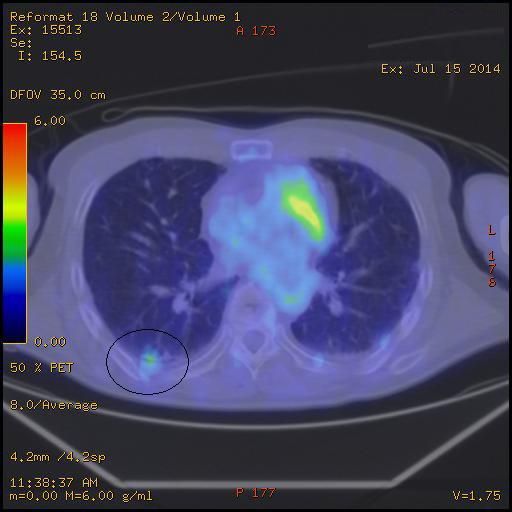

去年のペットがん検診から約1年

CT画像撮影で、1年前、半年前、今回と比較して炎症や傷みは進行が見られず でした。

とりあえず良かったです。

3か月後、肺機能検査を予約してきました。

胸椎の陰と腰椎の圧迫骨折は骨粗鬆症の治療薬を服用中